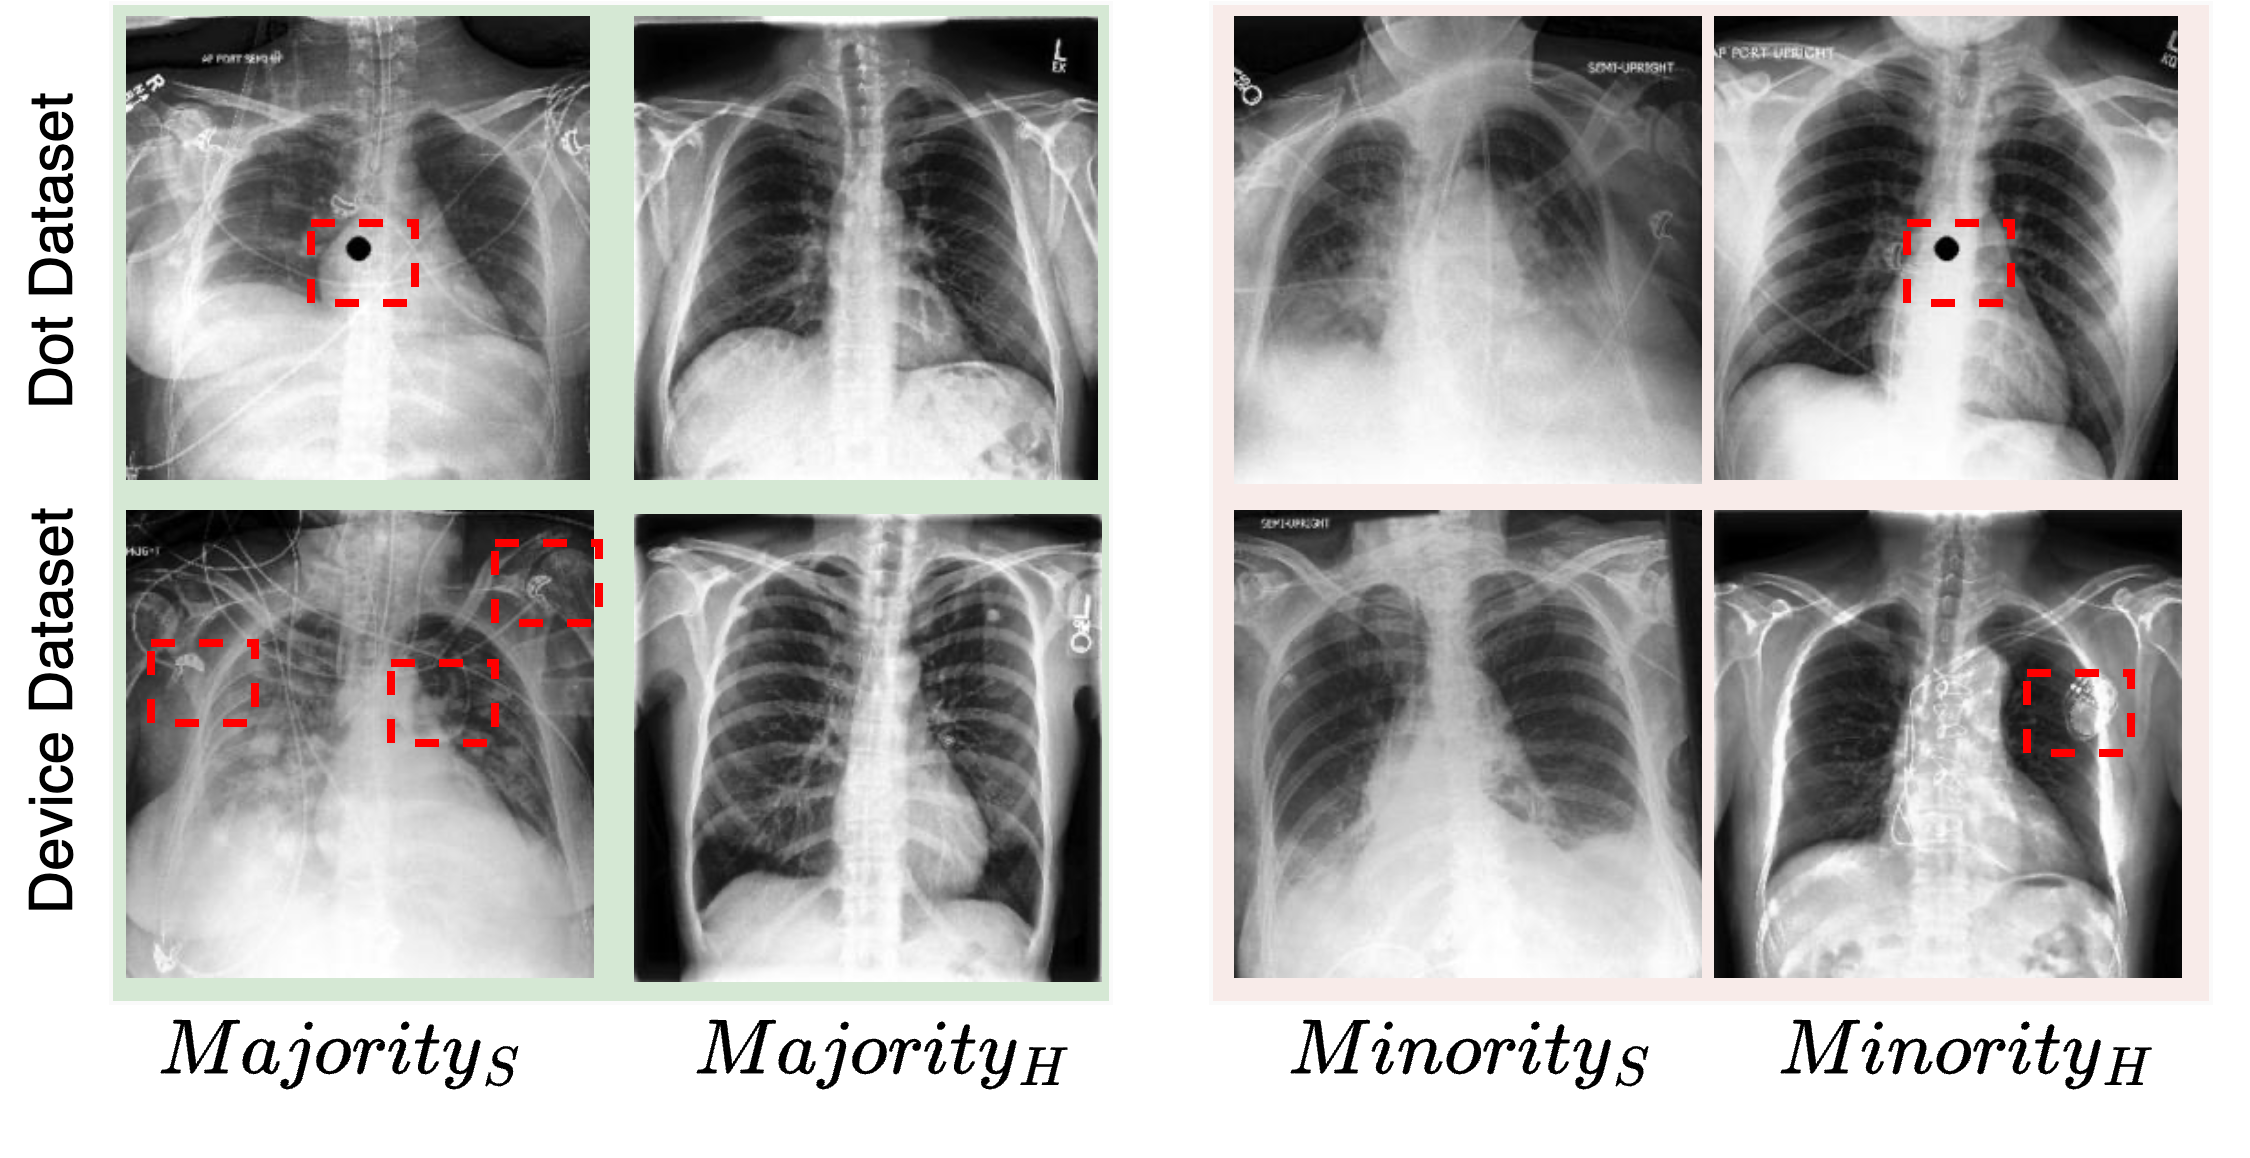

We perform experiments on the publicly available CheXpert dataset [Irvin et al.(2019)Irvin, Rajpurkar, Ko, Yu, Ciurea-Ilcus, Chute, Marklund, Haghgoo, Ball, Shpanskaya, et al.] that contains over 200,000 chest X-ray images, with binary labels for 14 diseases (e.g. Pleural Effusion, Cardiomegaly, Pneumonia), as well as binary labels indicating the presence of support devices (visual artifacts). We create two variants of the CheXpert dataset: (i) Dot dataset: We introduce a synthetic artifact, a black dot of radius 9 pixels, in the center of the image for evaluating the quality of counterfactual images in the presence of spurious correlations. This also helps to compare the behaviour of counterfactual images synthesized from the baseline method: DeCoDEx without a detector and the proposed DeCoDEx. (ii) Device dataset: A subset of the CheXpert data is used to demonstrate the performance of DeCoDEx in the presence of real artifacts (Support devices). In both datasets, the artifacts are present in the majority of images of subjects with Pleural Effusion and in the minority of images of healthy subjects. In contrast, the majority of the images of healthy subjects and the minority of the images of subjects with Pleural Effusion do not contain these artifacts. Fig. 3 shows the sample images from both the datasets and all four subgroups. For both datasets, the ratio of the number of samples in majority to minority is 90:10 and the dataset is divided into training/validation/testing with a 70/15/15 random split. The details of number of samples in different split is included in Appendix A.

Classifier and Detector evaluation The classifier’s performance on both datasets is shown in Table 2 on the row labeled ‘ERM’. Note that the performance on the minority subgroup samples is significantly lower than the majority for both datasets. The dot and device detectors perform very well with subgroups [, , , ] accuracies of [100, 99.9, 100, 99.8] and [91.8, 88.8, 79.2, 88.7]. Perfect accuracies for the dot detector can be expected given that the position and size of the dot remain fixed for all the subjects. However, the variability including size, position, intensity of support devices can be large, making detection much more challenging.